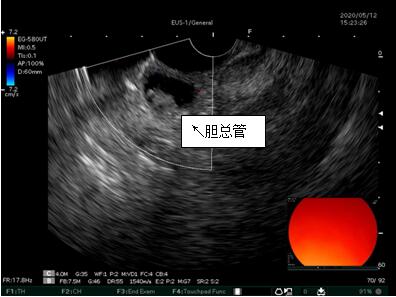

69歲王姓患者,因“發(fā)現(xiàn)無痛性黃疸1月”入院,根據(jù)患者病史,患者診斷傾向于壺腹部腫瘤所致梗阻性黃疸。予以完善腹部CT及上腹部MRI加MRCP均顯示肝內(nèi)外膽管擴(kuò)張,未發(fā)現(xiàn)明顯膽管,胰腺及十二指腸乳頭部腫瘤,且患者CA199正常。以前醫(yī)院未引進(jìn)超聲內(nèi)鏡,這類患者到此就遇到診斷瓶頸。此患者經(jīng)過消化內(nèi)科張丹霞副主任醫(yī)師完善超聲內(nèi)鏡檢查后,可以清楚顯示膽總管下段壁內(nèi)軟組織占位?;颊咄ㄟ^超聲內(nèi)鏡檢查診斷明確,轉(zhuǎn)至肝膽外科行手術(shù)治療。

超聲胃鏡圖片

膽總管小腫瘤性病變CT及MRI檢查陽性率偏低,因其低代謝特征,PET-CT陽性率也偏低,超聲內(nèi)鏡對這類疾病的診斷陽性率是所有檢查中最高的,且可行穿刺活檢進(jìn)一步確診病灶性質(zhì)。

環(huán)掃超聲內(nèi)鏡主要用于胃腸道粘膜下腫物診斷,胃腸道腫瘤分期,發(fā)現(xiàn)早期胃癌等,扇掃超聲內(nèi)鏡主要用于診斷膽道及胰腺疾病,并且可行穿刺活檢取病理。